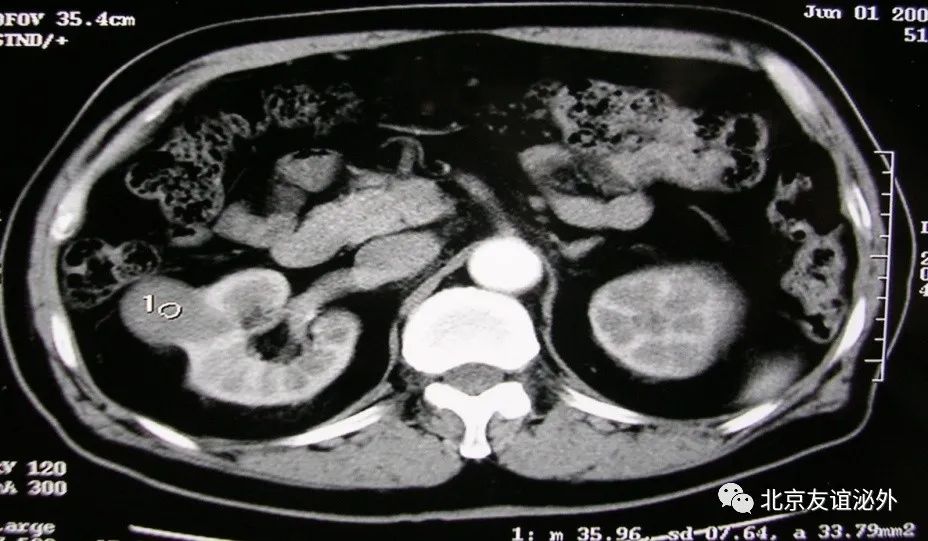

图1. Bosniak I级良性囊肿,是临床上最常见的囊肿